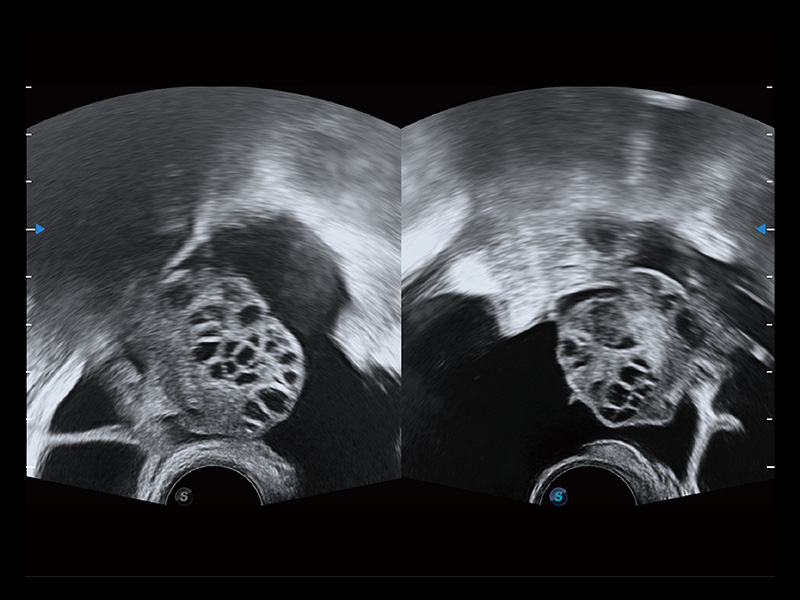

“生育问题”即关系民族复兴,也关系亿万家庭的幸福。随着婚育年龄推迟、社会压力增加等因素,越来越多人群也面临着“生不出、生不好”的问题。辅助生殖作为治疗不孕不育最有效的方法之一,也逐渐成为育儿新希望。而超声检查能为生殖需求人群的初诊评估提供宝贵的信息。 P20 Elite是新葡的京集团8814检测站匠心打造的一款生殖应用型彩超。她继承新葡的京集团8814检测站高端极光平台,突破性地将多款新型芯片及硬件模块进行整合,均衡了高端系统性能与小巧灵动机身。P20 Elite卓越的图像质量搭载专科探头,旨在为您提供全面的辅助生殖解决方案。

P20 Elite配备了丰富的生殖探头群和临床应用功能,在卵泡监测、穿刺取卵、胚胎移植、妊娠确认等领域,为生殖需求人群提供了新的临床机会,重新定义高端超声如何应用于生殖健康检查。

通过线上云会诊平台,实现县级医院与上级医院患者卵泡数据互联互通。避免重复性卵泡测量,提高诊断效率。